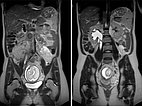

Koronare (oben) und axiale (unten) T2-gewichtete, fettunterdrückte Haste-Sequenzen ohne Kontrastmittel bei der Erstuntersuchung vor der Schwangerschaft.

Koronare (oben) und axiale (unten) T2-gewichtete Haste-Sequenzen ohne Kontrastmittel in der 21. Schwangerschaftswoche.